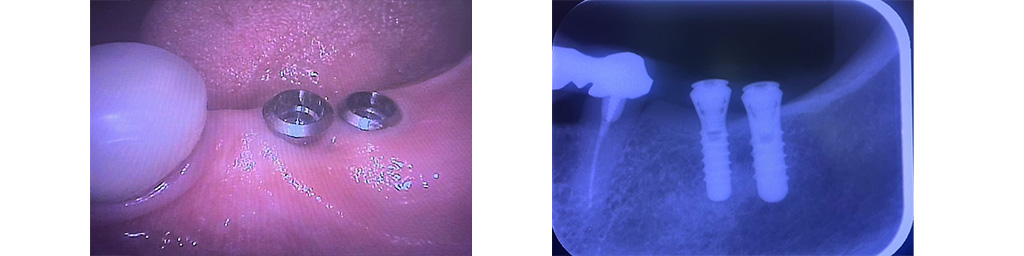

- ・歯科用CTによる三次元的な画像診断

- ・レントゲン撮影

などを行います。 この検査結果をもとに、インプラントを埋め込む位置や角度、本数、人工骨の必要性などを検討します。

インプラント治療では、顎の骨の量や厚み、神経や血管の位置を正確に把握することが欠かせません。当院では、

- 歯科用CTによる立体的な画像診断

また、材料メーカーとも連携しながら安全でレベルの高い治療を心がけていることも当院の特徴です。こうした設備や体制を活かし、インプラントを埋め込む位置や角度、必要に応じた人工骨の使用などを事前に検討し、より安全性に配慮した治療計画の立案をめざします。